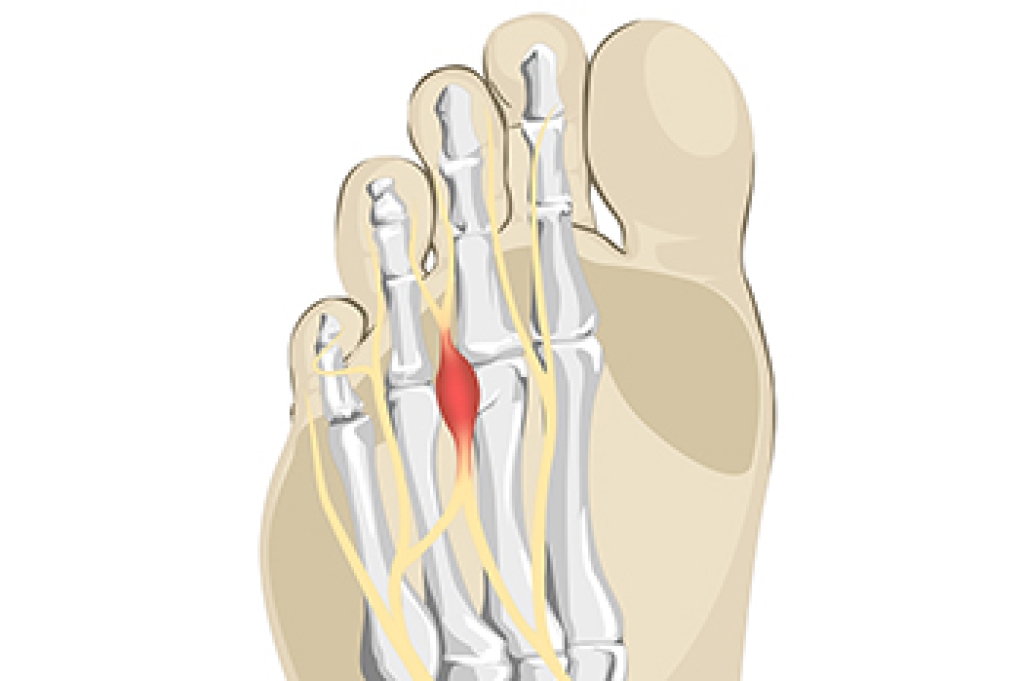

The plantar fascia is a thick band of tissue that is found on the sole of the foot, and connects the heel to the toes. An injury or repetitive stress may cause this area of tissue to become inflamed, and this is known as plantar fasciitis. Many people who are afflicted with this have severe pain and discomfort, and it is often difficult to walk. Symptoms can include a stabbing pain in the heel, which may be worse upon arising in the morning. When simple stretches are frequently practiced, they may help to reduce some of the discomfort caused by plantar fasciitis. A calf stretch is effective in strengthening the calf muscles. This is done by standing on a step, and lowering one heel at a time until a gentle stretch is felt. Some people find mild relief by placing the sole of their foot on a tennis ball, and rolling it for several seconds over the ball. Additionally, a towel crunch is practiced by placing a towel on the floor, and picking it up with the toes. If you would like more information about stretches to help reduce the pain from plantar fasciitis, please speak with a podiatrist.

Plantar fasciitis is one of the most common causes of heel pain. The plantar fascia is a ligament that connects your heel to the front of your foot. When this ligament becomes inflamed, plantar fasciitis is the result. If you have plantar fasciitis you will have a stabbing pain that usually occurs with your first steps in the morning. As the day progresses and you walk around more, this pain will start to disappear, but it will return after long periods of standing or sitting.